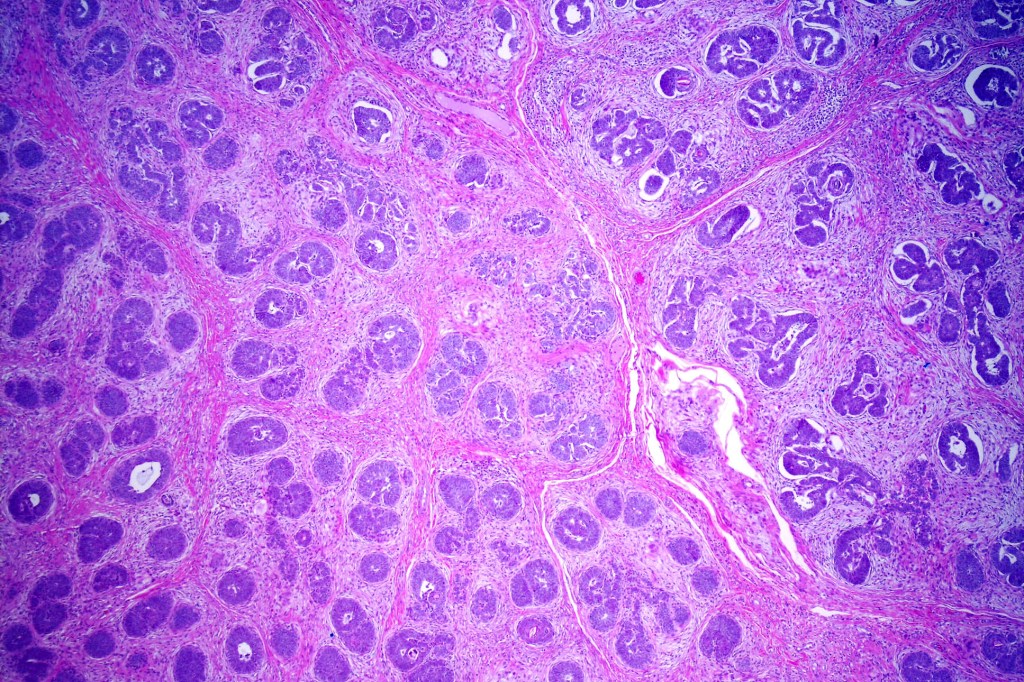

•Variably sized but generally large, basophilic tumor nodules composed of small uniform basaloid cells with minimal cytoplasm

•Peripheral palisading but no retraction artifact or stromal mucin deposition

•A rich fibromyxoid mesenchymal stroma with variable papillary mesenchymal bodies (sometimes these are absent)